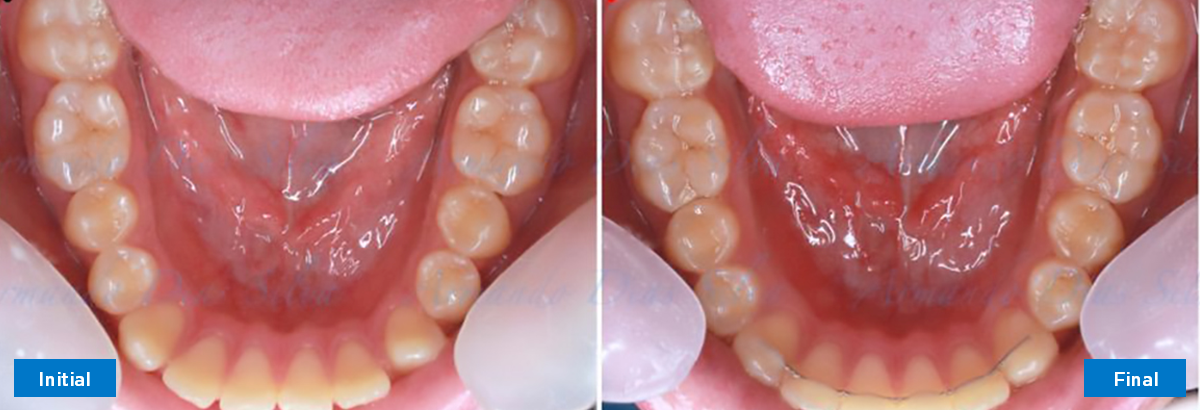

Clase II, Div. 1: Protrusión del incisivo central y espacios anteriores (SureSmile® Aligners)

Principal queja del paciente: Protrusión del incisivo central y mordida abierta. El paciente rechaza la expansión del arco palatino (MARPE) y las extracciones.

Este paciente adolescente presenta molares de Clase II y no le gusta su mordida abierta ni lo protrusivos que son sus dientes frontales. Por sus fotografías faciales, parece que su mandíbula es retrognática o le falta volumen en la barbilla. El historial del paciente también indica que existe un problema funcional al no haber guía de los incisivos.

Diagnóstico

• Molares de clase II

• Diastema

• Espaciamiento leve de las arcadas superior e inferior (deficiencia transversal de 3,45 mm)

• El primer molar superior derecho está en una posición más mesial que el primer molar superior izquierdo

• Deficiencia transversal maxilar leve (3,45 mm)

• Incisivos superiores e inferiores proclinados

• Orientación canina desfavorable

Se logran todos los objetivos principales:

• Molares de clase I logrados con distalización y sin elásticos

• Sin cambios en la posición del cóndilo

• Sin expansión maxilar, respetando la envoltura periodontal

• Incisivos inferiores retroinclinados, que mejoran la estabilidad a largo plazo